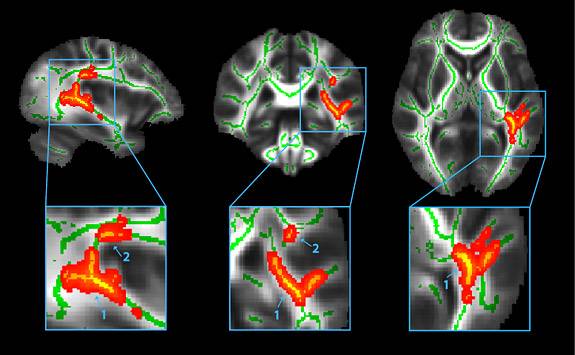

This diffusion tensor imaging scan of the human brain represents a combined image of the fiber tracts (nerve fibers that connect one area of the brain with another) located in the white matter of the brain of a group of 10 athletes who sustained a concussion and a control group of 10 athletes with no history of concussion. The three-dimensional scan shows the average image of all the white matter fiber tracts of the 20 subjects, with the center of the fiber tracts marked in green lines. The areas of the brain colored in red to yellow represent locations in which the concussed athletes show alterations in their white matter fiber tracts. The bottom images zoom in on the two main areas where the differences were found. (Image courtesy copyright Cubon et al. J Neuroscience 28:1-13, 2011)

Their current research builds on their pilot study published in the Journal of Neurotrauma in February 2011 with former Princeton neuroscience postdoctoral fellow Valerie Cubon and Cynthia Boyer of Bancroft NeuroHealth. In that study, DTI scans were performed on 10 concussed student-athletes with prolonged symptoms such as headaches, dizziness and trouble concentrating, which they experienced for at least six weeks to more than a year. The scans provided evidence of structural differences in the brain, suggesting that DTI may be a useful tool to evaluate concussive injury.